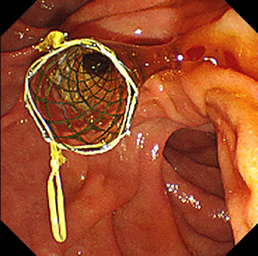

内視鏡的乳頭括約筋切開術

高周波電流で十二指腸乳頭部(胆管開口部)を一部凝固切開し、胆管結石を取り出します。

急性胆管炎の治療の際は、専用のバスケットカテーテルで総胆管内の胆汁を十二指腸や体外に排出できるようにステントを揷入留置します。

内視鏡的乳頭括約筋切開術(EST)

バスケット採石気管支鏡